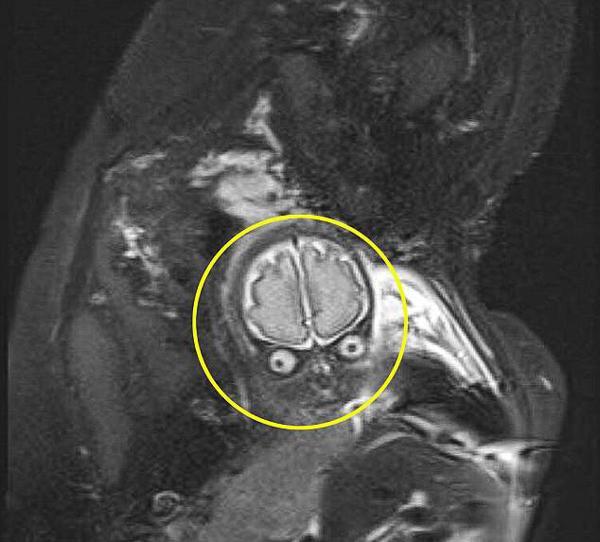

Hình ảnh siêu âm từng gây "sốt" vì không khác gì khuôn mặt chúa tể hắc ám.